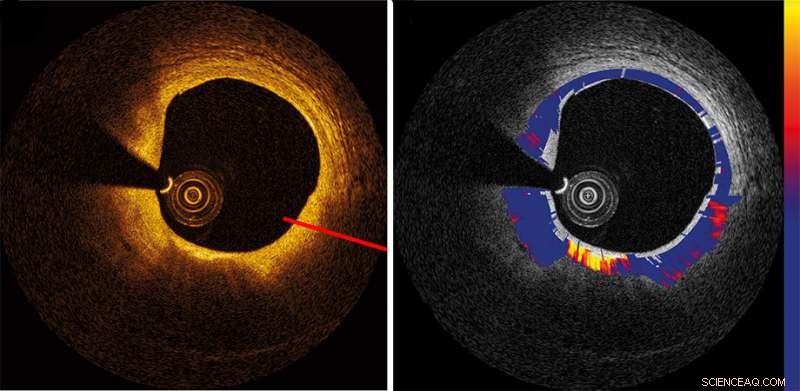

From Fig. 3, DOI: 10.1117/1.JBO.25.4.040901 Credit: SPIE

Based on the backscattered signal produced when an optical beam encounters living tissue, OCT enables researchers and clinicians to quantify structural thickening associated with various pathologies—from age-related macular degeneration to certain forms of cancer growth. But there are some ultra-small-scale changes in tissue morphology during the onset and progression of diseases beyond the scope of conventional clinically available imaging techniques. To capture such subtle yet significant changes, an important complement to standard OCT is quantitative measurement of the attenuation of the OCT signal. Signal attenuation can convey important information about the strength of the backscattered signal—like an echo composed of light, as it fades, it provides valuable information about the optical properties of the biological tissue.